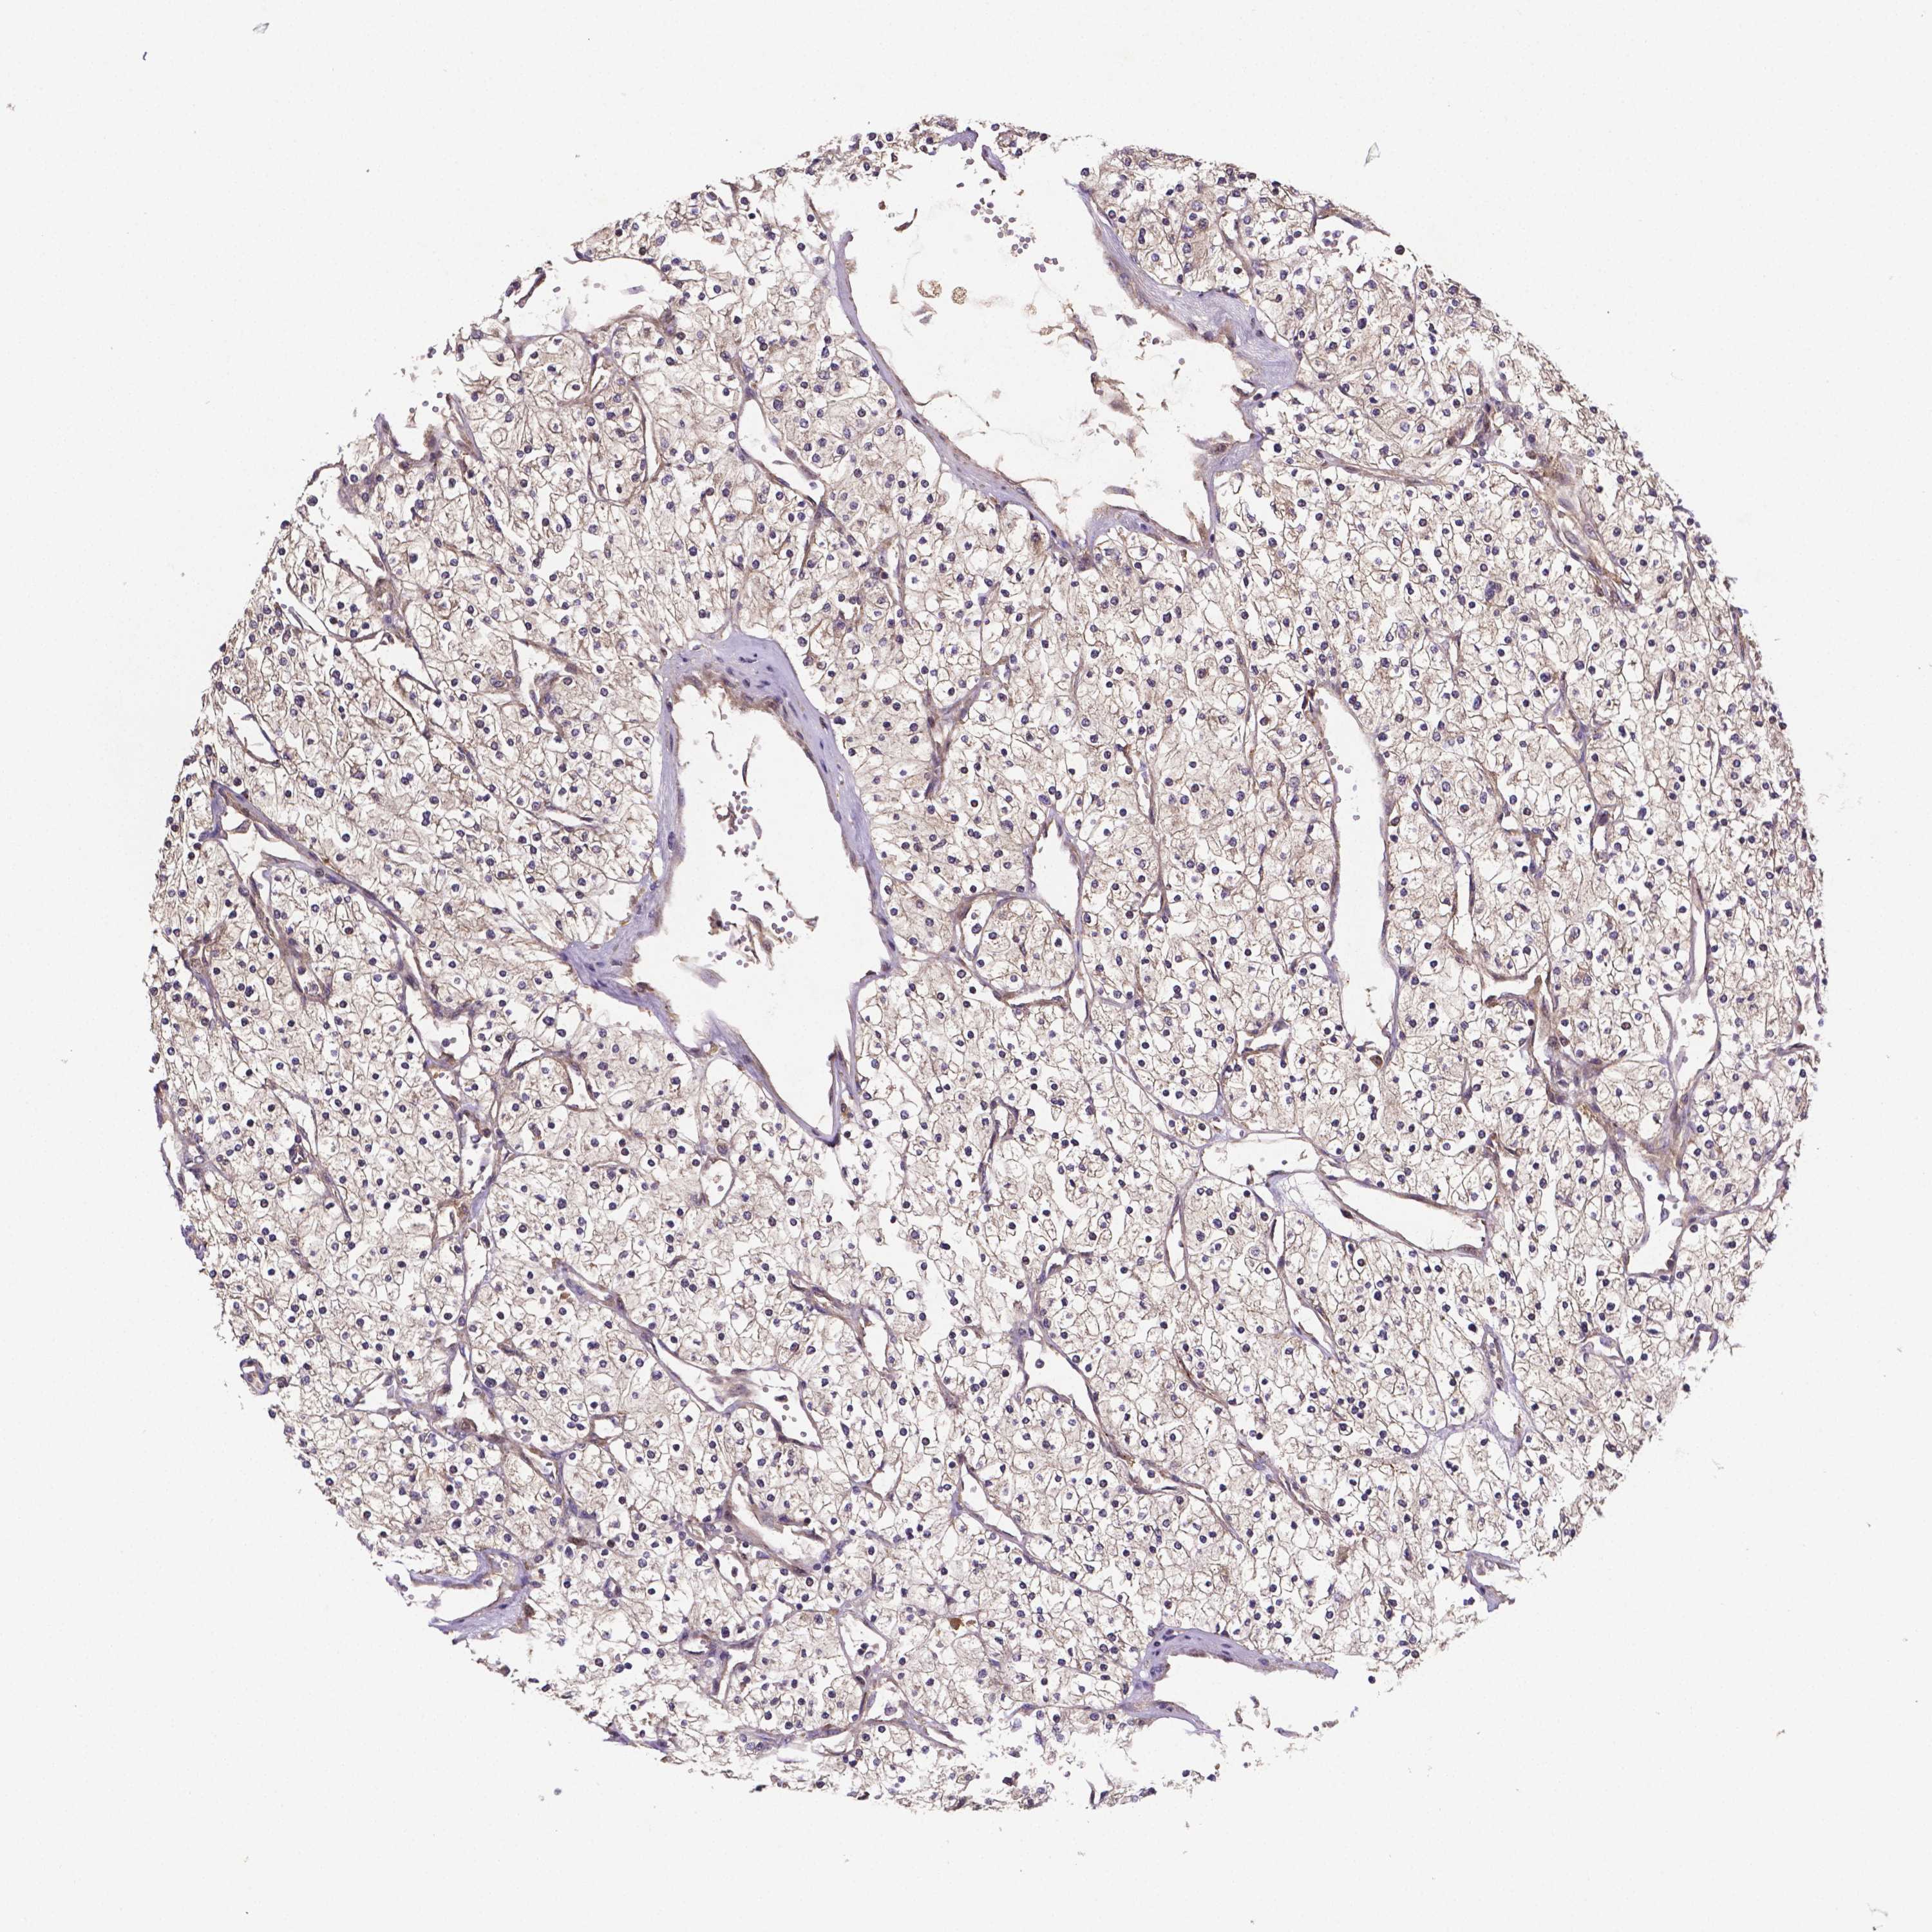

KIDNEY RENAL CLEAR CELL CARCINOMA (VALIDATION) - Interactive survival scatter ploti

The Survival Scatter plot shows the clinical status (i.e. dead or alive) for all individuals in the patient cohort, based on the same data that underlies the corresponding Kaplan-Meier plots. Patients that are alive at last time for follow-up are shown in blue and patients who have died during the study are shown in red.

The x-axis shows the expression levels (FPKM) of the investigated gene in the tumor tissue at the time of diagnosis. The y-axis shows the follow-up time after diagnosis (years). Both axes are complimented with kernel density curves demonstrating the data density over the axes. The top density plot shows the expression levels (FPKM) distribution among dead (red) and alive patients (blue). The right density plot shows the data density of the survived years of dead patients with high and low expression levels respectively, stratified using the cutoff indicated by the vertical dashed line through the Survival Scatter plot. This cutoff is automatically defined based on the FPKM cutoff that minimizes the p-score. The cutoff can be changed by dragging the vertical line or by entering a cutoff value in the square labeled "Current cut-off".

Under the Survival Scatter plot the p-score landscape (black curve; left axis) is shown together with dead median separation (red curve; right axis). Dead median separation is the difference in median mRNA expression between patients who have died with high and low expression, respectively. It is calculated as follows: median FPKM expression of dead patients with high expression - median FPKM expression of dead patients with low expression. This is intended to aid the user in visually exploring custom cutoffs and the associated p-scores and dead median separation.

Individual patient data is displayed and can be filtered by clicking on one or more of the category buttons on the top of the page. Categories describing expression level and patient information include: high, low, alive, dead, female, male and tumor stages. The scale of the x-axis can be toggled between linear and log-scale by clicking on the "x log" button. Mouse-over function shows TCGA ID, patient information and mRNA expression (FPKM) for each patient.

& Survival analysisi

Kaplan-Meier plots summarize results from analysis of correlation between mRNA expression level and patient survival. Patients were divided based on level of expression into one of the two groups "low" (under cut off) or "high" (over cut off). X-axis shows time for survival (years) and y-axis shows the probability of survival, where 1.0 corresponds to 100 percent.

RNF123 is not prognostic in Kidney Renal Clear Cell Carcinoma (validation)

Best expression cut offi

Based on the FPKM value of each gene, patients were classified into two groups and association between prognosis (survival) and gene expression (FPKM) was examined. The best expression cut-off refers the FPKM value that yields maximal difference with regard to survival between the two groups at the lowest log-rank P-value. Best expression cut-off was selected based on survival analysis .

When clicking on this number, the vertical dashed line indicating cut-off, the interactive survival plot, and the Kaplan-Meier curve will be adjusted to show results based on the best expression cut-off.

: 10.15

P scorei

Log-rank P value for Kaplan-Meier plot showing results from analysis of correlation between mRNA expression level and patient survival.

N/A

TCGA RNA samplesi

RNA-seq data is reported as average FPKM (number Fragments Per Kilobase of exon per Million reads), generated by the The Cancer Genome Atlas (TCGA) .

Normal distribution across the dataset is visualized with box plots, shown as median and 25th and 75th percentiles. Points are displayed as outliers if they are above or below 1.5 times the interquartile range. FPKM values of the individual samples are presented next to the box plot.

Average pTPM 11.1

Number of samples 100